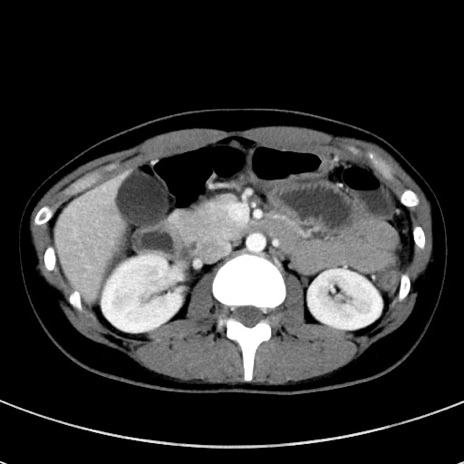

症例17(横断像)

【症例】20歳代女性

【主訴】嘔吐、下腹部痛

【現病歴】昨日夕食後に嘔吐し下腹部痛が出現。本日になっても嘔吐持続し改善しないため来院。

【身体所見】意識清明、BT 37.2℃、BP 108/67mmHg、腹部:平坦、やや硬、下腹部正中から右にかけて圧痛あり、反跳痛軽度あり、tapping pain(+)。

【データ】WBC 13600、CRP 14.94